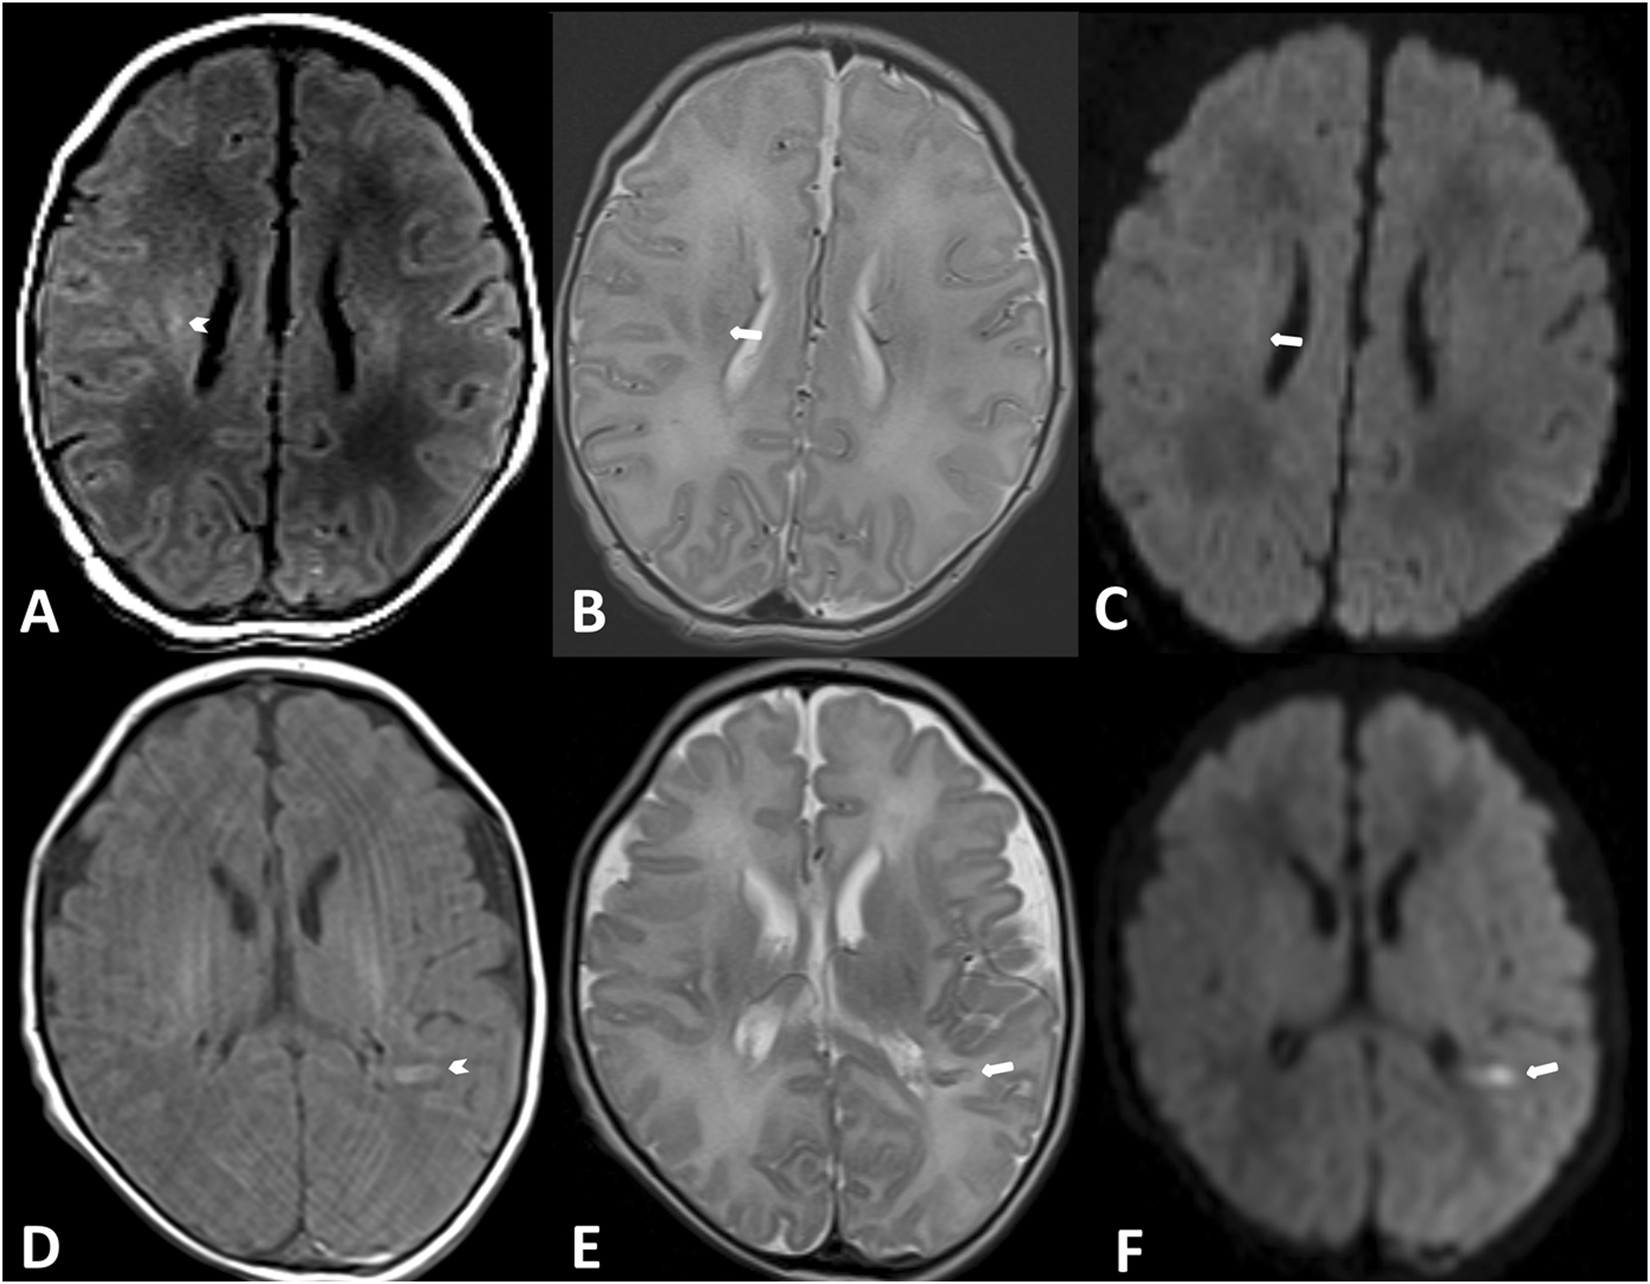

Figure 2

Examples of a WMI (upper row) and a stroke (lower row). A WMI is seen in the right semioval centre with T1w hyperintense signal intensity and no signal changes in T2w and DWI (patient No. 8). An acute stroke is seen in the white matter on the left, with signal changes in T1w and T2w and diffusion restriction in the DWI (patient No. 3).